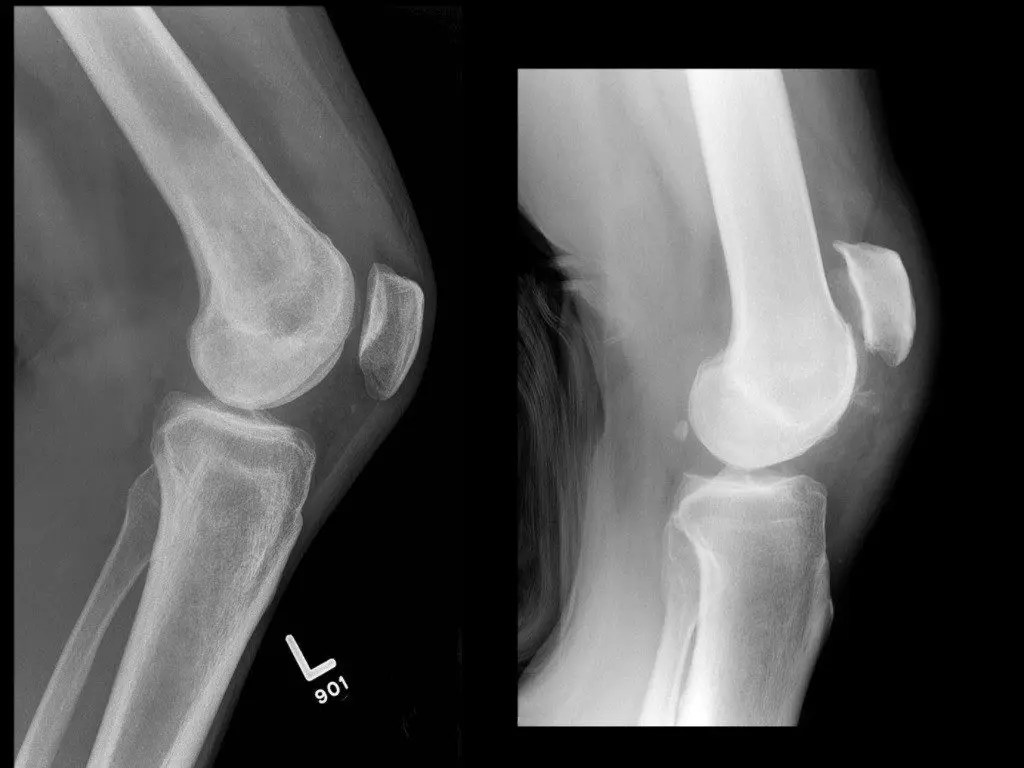

Quadriceps Tendon Rupture —

Bilateral Quadriceps Tendon Rupture — Knee Brace For Quadriceps Tendon Rupture Diagnosis is made clinically with. There may also be a small piece. A quadriceps tendon rupture is a traumatic injury of the quadriceps insertion on the patella leading to a disruption in the knee extensor mechanism. These are fabulous braces and are very. It almost always requires surgery, followed by physical therapy to regain full knee motion and function. A. Knee Brace For Quadriceps Tendon Rupture.

Quadriceps Tendon Rupture — Knee Brace For Quadriceps Tendon Rupture Ruptures of the quadriceps tendon occur relatively infrequently and usually occur in patients older than 40 years. There may also be a small piece. Quadriceps tendon tears are not. This protocol is time based (dependent on. Hinged rom knee brace, post op knee brace for recovery stabilization. These are fabulous braces and are very. A quadriceps tendon rupture is a. Knee Brace For Quadriceps Tendon Rupture.